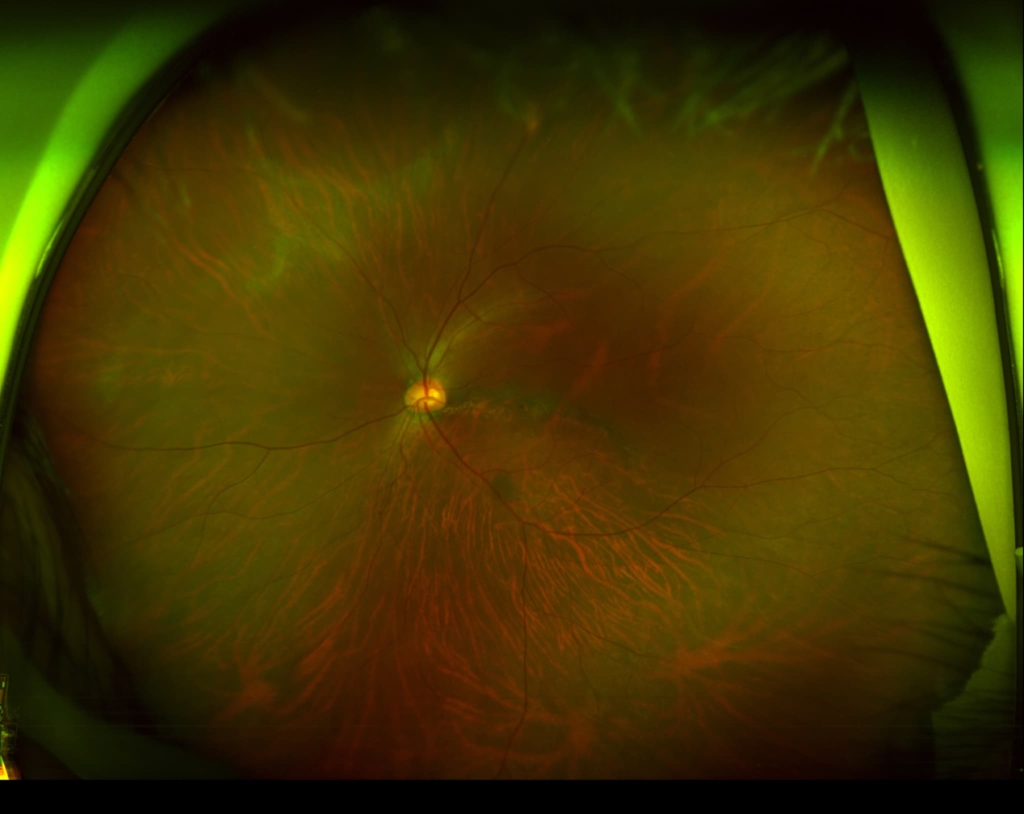

乳頭が下鼻側に傾斜し、下方に萎縮(PPA)がみられる。

両眼ともに、後部ぶどう腫staphylomaの上縁に一致して乳頭下縁から黄斑を横断するように帯状の網脈絡膜の萎縮巣がみられる。また後部ぶどう腫領域に一致して網膜・脈絡膜が菲薄化しているため、紋理眼底tessel lated fundusがみられる。